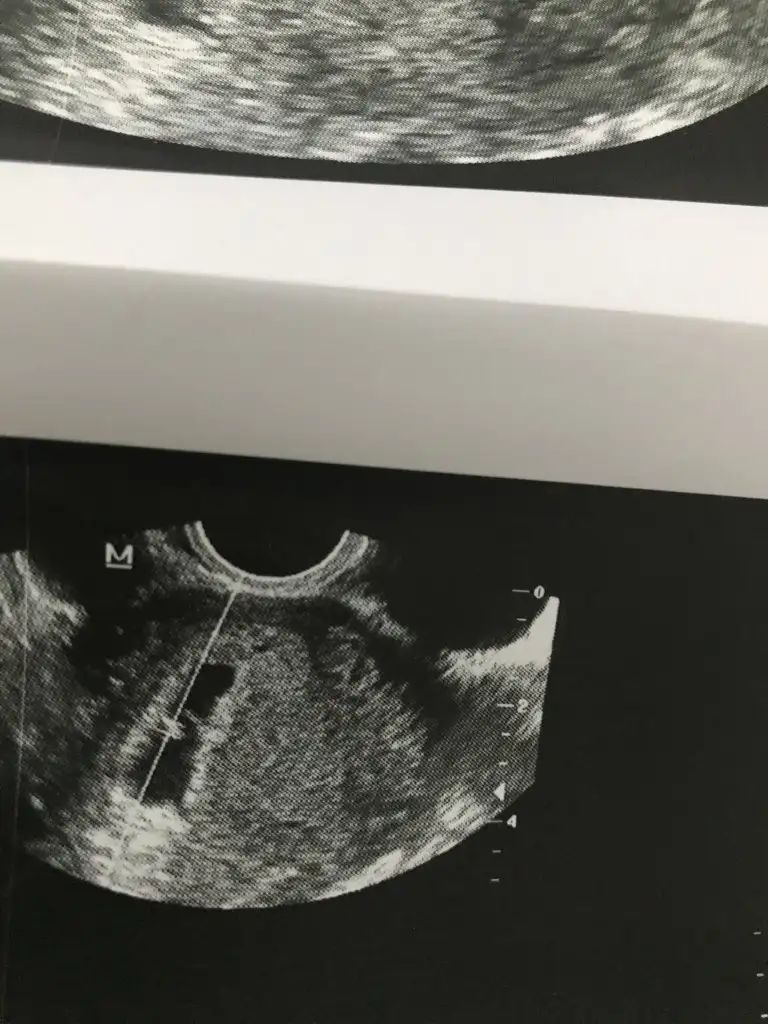

bnmde 5 +4 ken ultrasyonda baktırdım daha minik duruyodu benmki :)5+2 haftalık 14.44 mm yazıyo kağıtta

Inşallah canım benim Rabbim hayırlı sağlıklı sıhhatli hamilelik geçirmeyi nasip etsin inşallah cümlesiyle benimde regle tarihime göre 7+6 olması lazım ama şuan 7+2 braz geriden geliyormaşallah erken duymussunuz darısı basıma inş :)ben 1 hafta daha beklemeyi düşünüyorum regl tarihien göre su an tam 6

işte bana onu slemediler su kadarlık bu kadarlık diye doktorlar sormadan bsy sölemiyorki buralardan öğreniyoruz cogu seyi 2 kere ultrasyona girdim net olarak su kadar demediler heralde cok küçük oldugu için :)Inşallah canım benim Rabbim hayırlı sağlıklı sıhhatli hamilelik geçirmeyi nasip etsin inşallah cümlesiyle benimde regle tarihime göre 7+6 olması lazım ama şuan 7+2 braz geriden geliyor